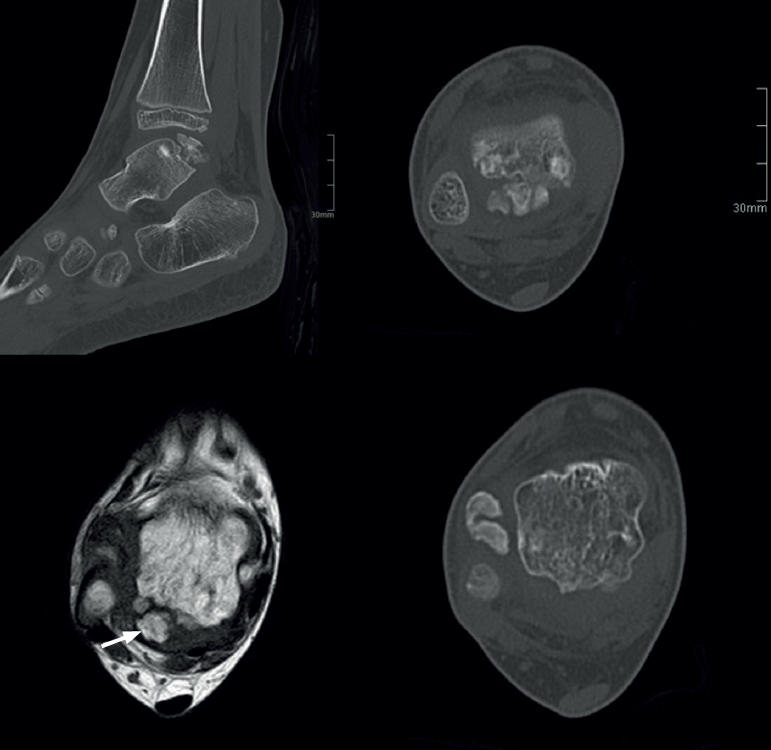

Es una entidad rara de etiología desconocida que afectaría a 1 de cada millón de personas, es 3 veces más frecuente en el varón y presenta el aspecto clínico e histológico de un osteocondroma que asienta en la epífisis en vez de la zona metafisaria del hueso en crecimiento(24,25)(Figuras 4 y 5).

Radiológicamente, se caracteriza clásicamente por(23):

- Crecimiento óseo no uniforme.

- Centros de osificación desconectados de la epífisis.

En adultos (Figuras 6 y 7), se cita como causa de pinzamiento doloroso en la cámara posterior del tobillo(50), aunque también como causa de impingement anterior(51), o confundirse con un osteocondroma a pesar de sus diferencias histológicas. Mientras el osteocondroma reproduce una arquitectura similar a la de la placa de crecimiento, la displasia epifisaria hemimélica muestra en su cubierta cartilaginosa áreas con acúmulos de condrocitos y pequeñas áreas de cartílago calcificado no reabsorbido(52). Por otra parte, la presencia de osteocondromas en la parte posterior del astrágalo es muy rara. En una serie de 7 casos en los que se produjo rotura a través del pedículo en relación con ejercicio físico, Carpintero et al. no señalan ninguna en esta localización(53).